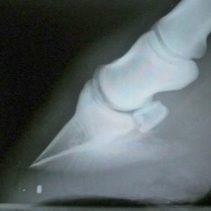

Le pied du cheval a deux cartilages latéraux qui sont reliés aux ailerons de la troisième phalange. Ces cartilages bougent lorsque l'animal est en mouvement et leurs extrémités sont visibles au-dessus de la couronne (dans le talon) de chaque côté du pied. Chez les chevaux âgés, les cartilages s'ossifient ce qui est un phénomène de vieillissement normal. Les cartilages ossifiés perdent leur souplesse et sont appelés des formes cartilagineuses.

Ce phénomène est plus courant chez les trotteurs que chez les chevaux de selle et occasionne rarement la boiterie, sauf si le cartilage ossifié est endommagé (fracturé ou blessé).

Chez les jeunes chevaux, des chocs répétés peuvent causer des douleurs et une inflammation tissulaire autour des cartilages d'où une ossification prématurée. Bien que les formes cartilagineuse soient souvent décelées par rayons X, elles provoquent rarement la boiterie mais occasionnent d'autres troubles. Si une douleur et une inflammation sont décelées à la couronne, le cheval doit rester au repos.